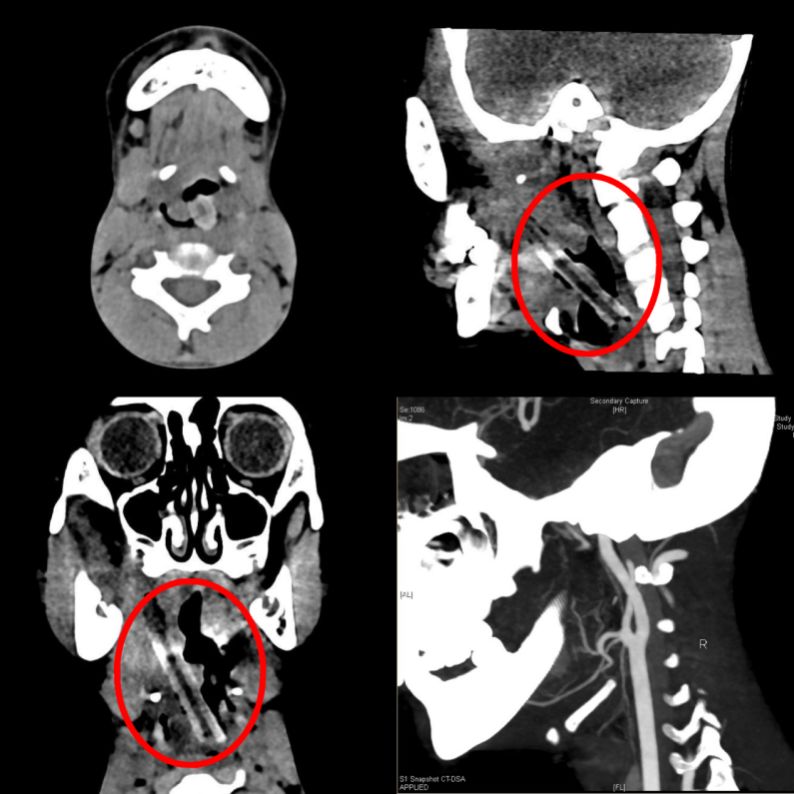

CT檢查圖片可見樹枝位置

檢查結(jié)果顯示,長達(dá)5厘米的樹枝從小李右側(cè)咽旁延續(xù)至左側(cè)梨狀窩,這個粗大的樹枝隨時影響到旁邊狹窄氣道的通氣與進(jìn)食。

由于殘留的樹枝位置較深,從小李咽旁間隙跨過會厭,一直插入左側(cè)咽旁間隙。這樣一個“野蠻”的樹枝隨時會導(dǎo)致出血阻塞呼吸道,處理起來十分棘手。